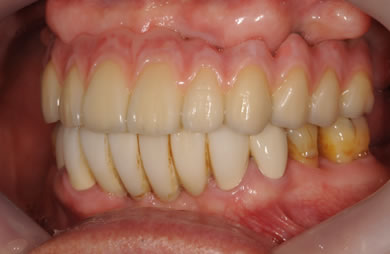

インプラントの症例写真 IMPLANT

骨再生スピードインプラント治療+AGC連結セラミック治療+セラミック治療

| 治療方針 | ソケットリフト法により上顎洞底部を拳上することにより、骨の無い部分に骨をつくってあげ、インプラント治療を可能にする。さらに歯周病により組織の破壊が著しいので、AGC連結セラミック治療により上顎の審美的回復を行う。 | ||||||||||||||||||||||||||||||||

| 治療内容 | インプラント7本(抜歯AGC即日スピードインプラント+ソケットリフト)、AGCハイブリッドセラミック連結ブリッジ1装置(上顎)ハイブリッドセラミック8本 | ||||||||||||||||||||||||||||||||